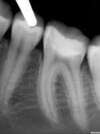

REMPLACEMENT D'UN AMALGAME CARIE PAR UN ONLAY CERAMIQUE E-MAX, CAS DU DR MAXIME COLLANGETTES

Une jeune patiente se présente avec une reconstitution métallique non étanche sur une première molaire mandibulaire.

Il est décidé de réaliser une reconstitution en Onlay céramique type E-Max (c) qui sera ensuite collée sous digue.

Le contrôle radiographique montre le parfait ajustage